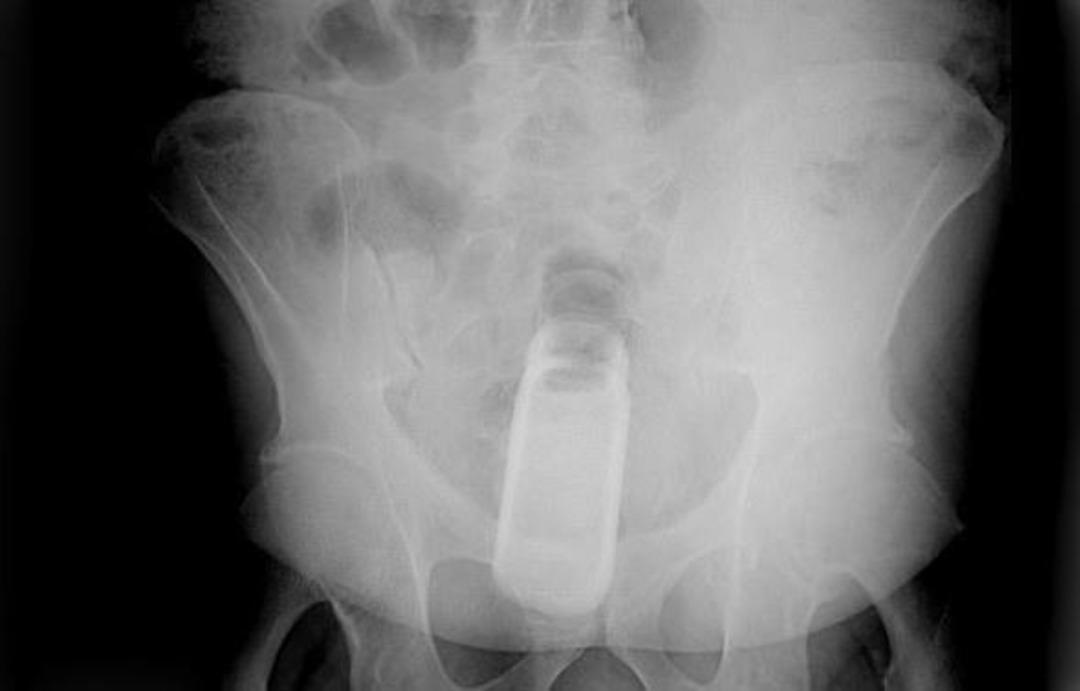

Açıklanan raporlar arasında acil durum şikayetiyle ilgili olan görenleri hayrete düşürdü. Oldukça ilginç bulunan bu raporda röntgen cihazlarda çekilen filmler yer aldı. Bakın o filmlerde nasıl görüntüler vardı?

Röntgen filmlerinden öyle şeyler çıktı ki...